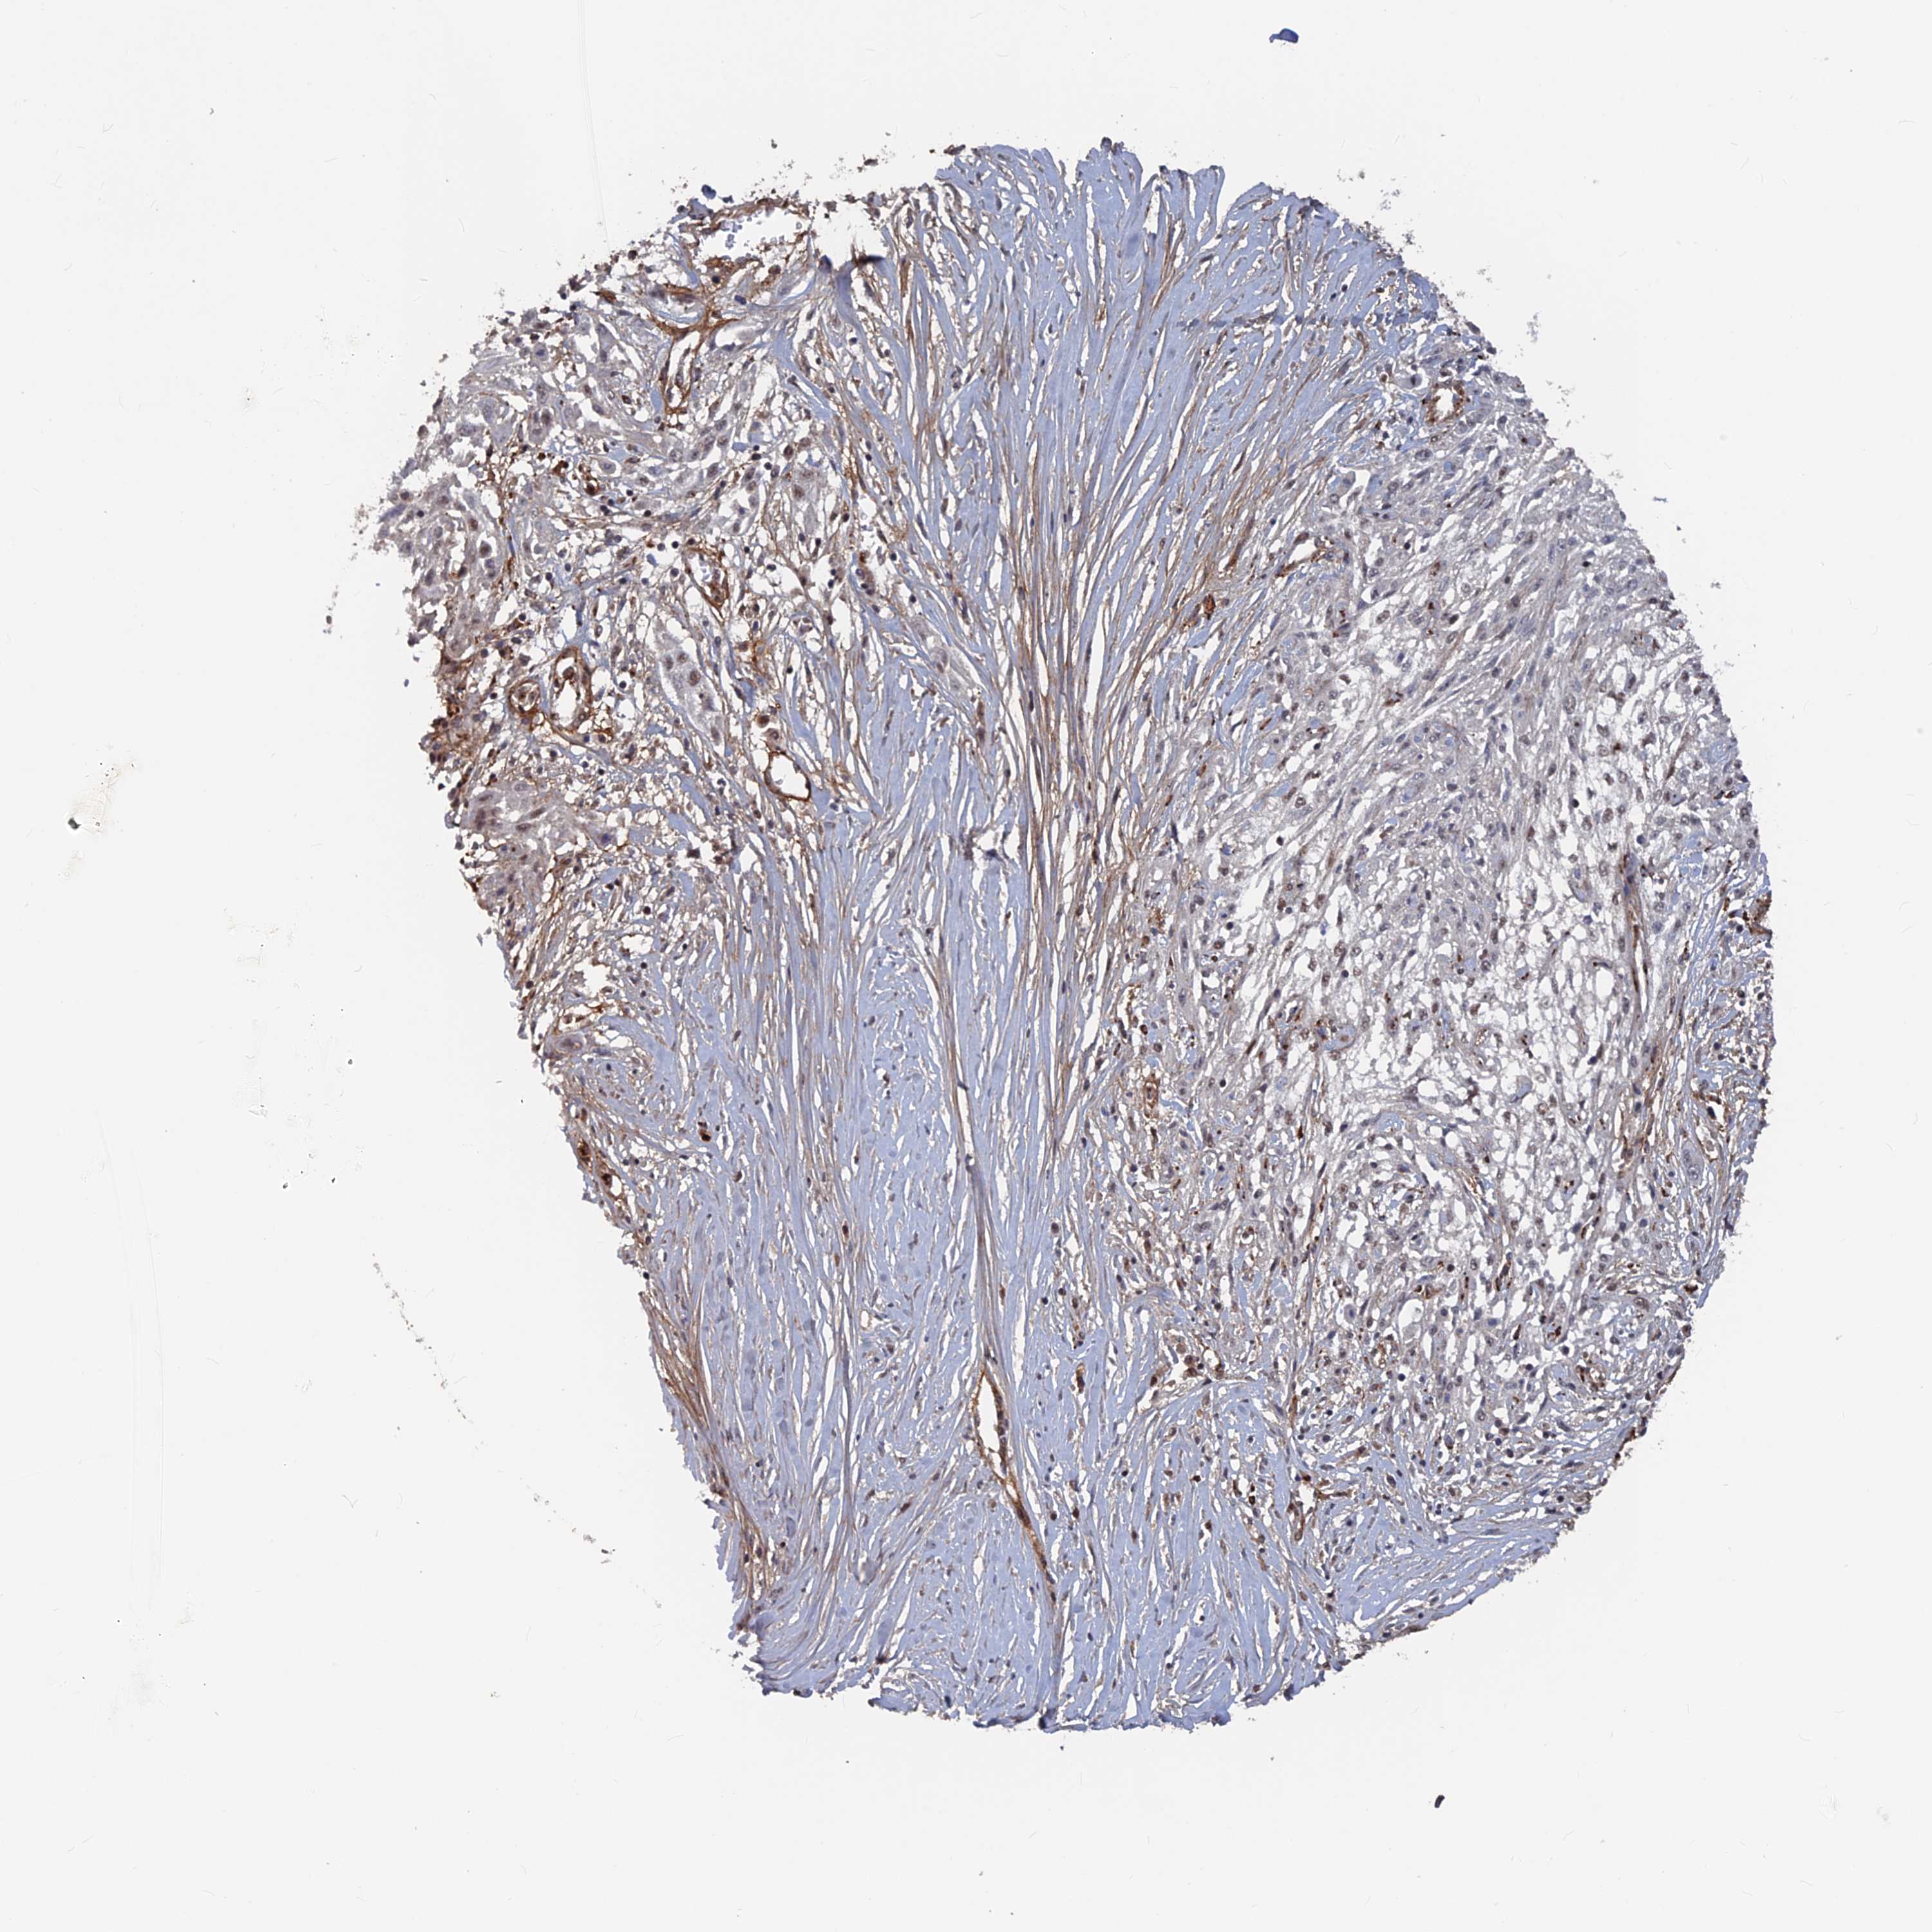

Basal cell and squamous cell cancer

SKIN CANCER - Protein expressioni

A mouse-over function shows sample information and annotation data. Click on an image to view it in a full screen mode. Samples can be filtered based on level of antibody staining by selecting one or several of the following categories: high, medium, low and not detected. The assay and annotation is described here.

Each image is clickable and will lead to virtual microscopy that enables deeper exploration of all samples and also displays staining intensity scores, fraction scores and subcellular localization as well as patient and tissue information for each sample.

Antibody HPA042212

Antibody HPA042456

Squamous cell carcinoma, metastatic, NOS